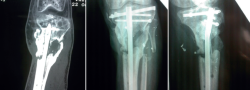

A los 11 meses, el paciente presenta un balance articular completo de la rodilla, aunque refiere dolor en la zona de la fractura. Tras realizarle las pruebas radiológicas pertinentes, se observa la presencia de una pseudoartrosis en el foco de fractura, complicación más que esperable en este paciente (Figuras 10 y 11).

retla.05210.fs2209019-figura10.png

Figura 10. A los 11 meses se evidencia la falta de consolidación, pseudoartrosis.